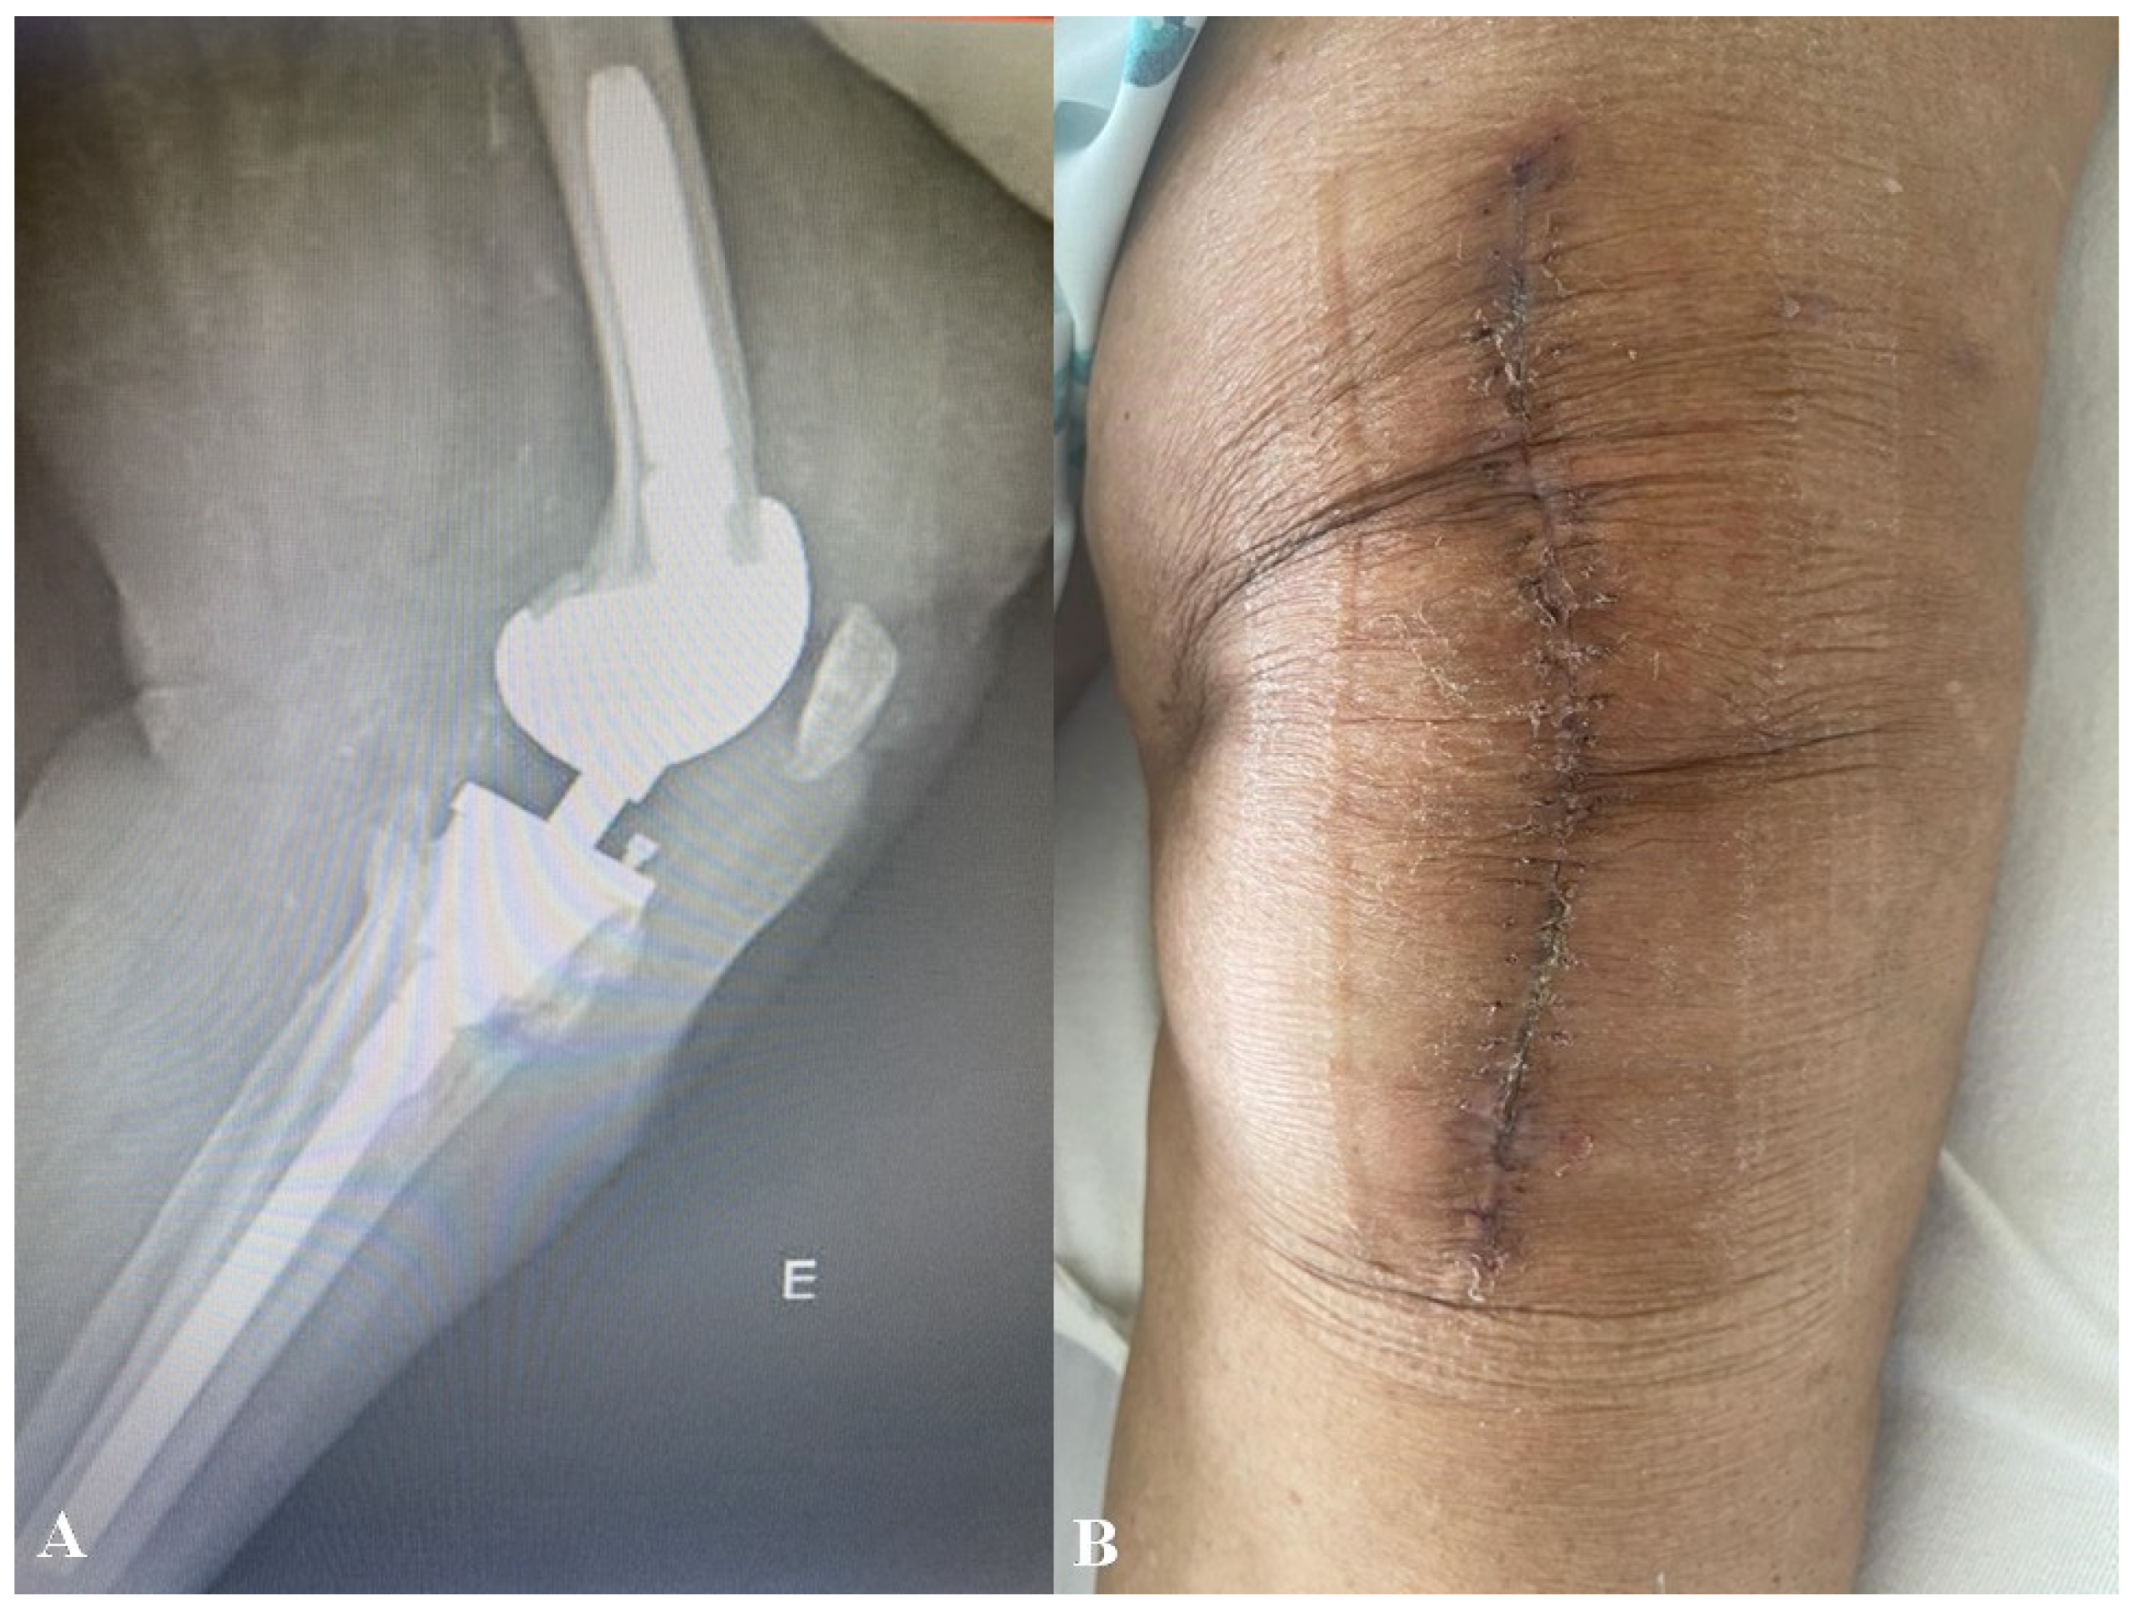

2. Case Report